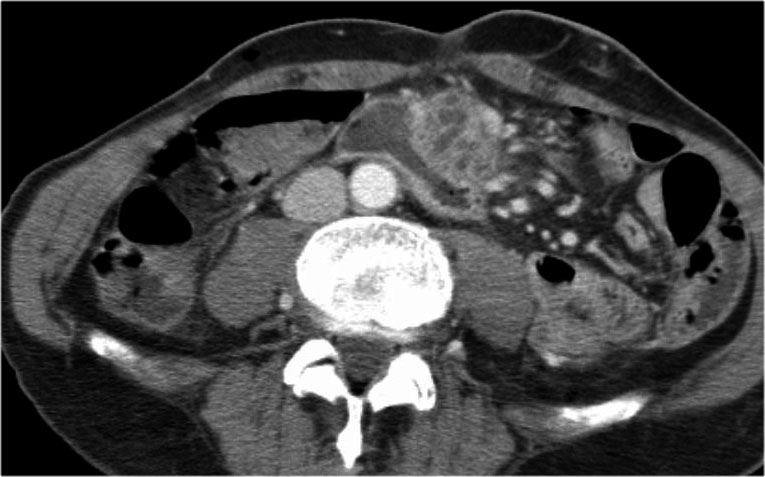

Hình ảnh CT cho thấy một nang lớn ở vùng thượng vị trên bệnh nhân có tiền sử viêm tụy cấp (Hình).

Lưu ý có thêm một ít dịch cổ trướng và dịch màng phổi.

Thành nang có ngấm thuốc.

CT cho thấy hai nang lớn ở bệnh nhân nữ 45 tuổi có tiền sử chấn thương (hình).

Lưu ý hình ảnh thâm nhiễm mỡ trong khoang sau phúc mạc (mũi tên).

Kết hợp đặc điểm hình ảnh với tiền sử lâm sàng, rất có khả năng đây là các nang giả tụy do chấn thương.